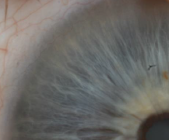

סימנים אירידולוגים בקשתית העין לאבחון אטופיק דרמטיטיס

דרך העין ניתן לראות את מצב האיברים, המערכות והרקמות בגוף ובעזרת האבחון האירידולוגי, לאבחן את מצבו של המטופל, נטיותיו הגנטיות ועוד ובכך לדייק את הטיפול עבורו.

פעמים רבות קיים קושי באבחון מצב המטופל. מה הבעיה ממנה סובל? מה הגורם? מה השתבש בגוף שגרם להתפרצות? מה יצא מאיזון.. האירידולוגיה עוזרת לנו לראות מה קורה בתוך הגוף, ברקמות והאיברים ומדייקת את הטיפול ספציפית למטופל. תנו לי לחשוף אתכם לעולם מופלא, נגלה כיצד ניתן לראות מה קורה בתוך הגוף, מה הם הסימנים בקשתית העין היכולים לשקף את מצב הגוף, הנטיות הגנטיות ועוד ובכך לסייע לנו לאבחן ולהתאים טיפול מדוייק בהרבה לחולי אטופיק דרמטיטיס (אסתמה של העור).

אירידולוגיה היא שיטת אבחון ע"י התבוננות בקשתית העין. כשרק נוצרנו ברחם אמנו היינו דיסקית הנסגרה לצינור שעתיד להתפתח לגופנו. קצהו של הצינור אשר עשוי מכל השכבות התאים המרכיבות אותנו עתיד להיות בסופו של דבר קשתית העין. משמע, קיימות שלוחות לכל איבר ומערכת בגופנו בקשתית ודרכה ניתן לראות את מצבם, לאבחן פתולוגיות או בעיות בתפקוד אתם איברים או מערכות ולהבין מה בדיוק קורה שם.

Lymphatic pure

סיבים צפופים בצבע תכלת, אפור ולבן המרמזים על היפראקטיביות של מערכת החיסון, נטייה לאלרגיה בעור, פתולוגיות נשימתיות, עודף היסטמין (חומר הקשור לתהליכים אלרגנים) ועוד.